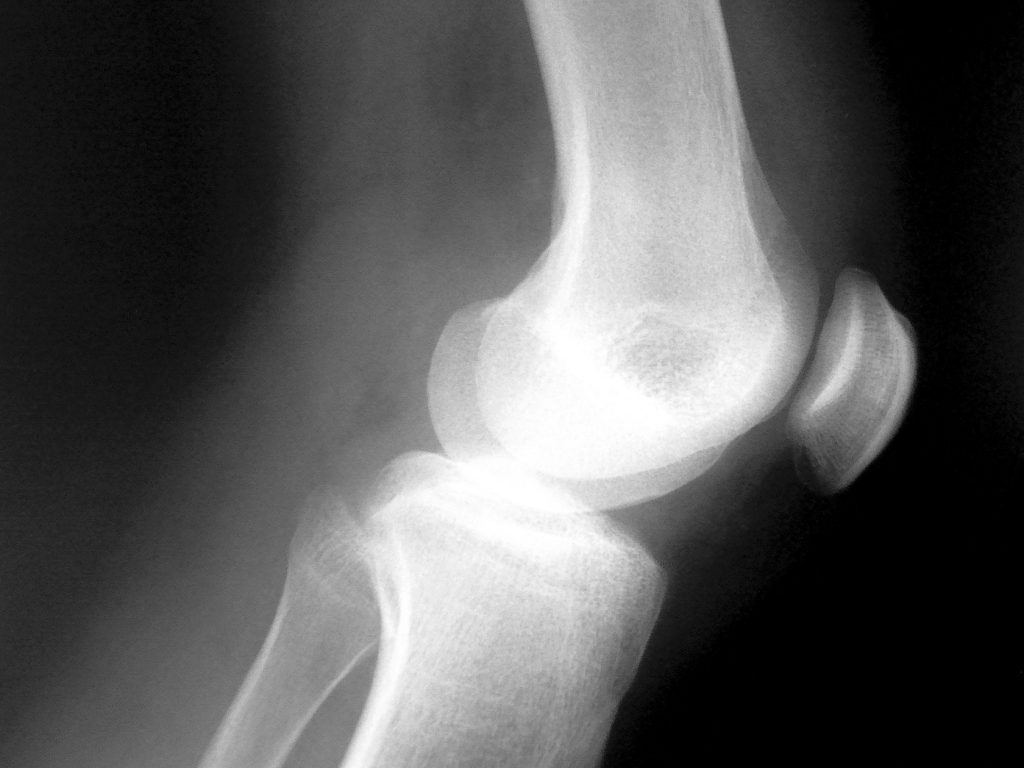

Ten years ago I started feeling mild discomfort when I squeezed my thumb and forefinger together (like plucking stray hairs, etc.), which has worsened over the years to the point of severe pain at times. Four years ago I had X-rays of both hands showing degradation of the basal thumb joint on both hands, more severe on the right. This week I had another set of X-rays that showed the right hand thumb joint to be filled with calcium, bone spurs, no joint space – the doc said “no wonder that hurts”. The metacarpal bone is being pushed out of alignment and the joint is deforming visibly. The left hand is better, but the same process is at work.